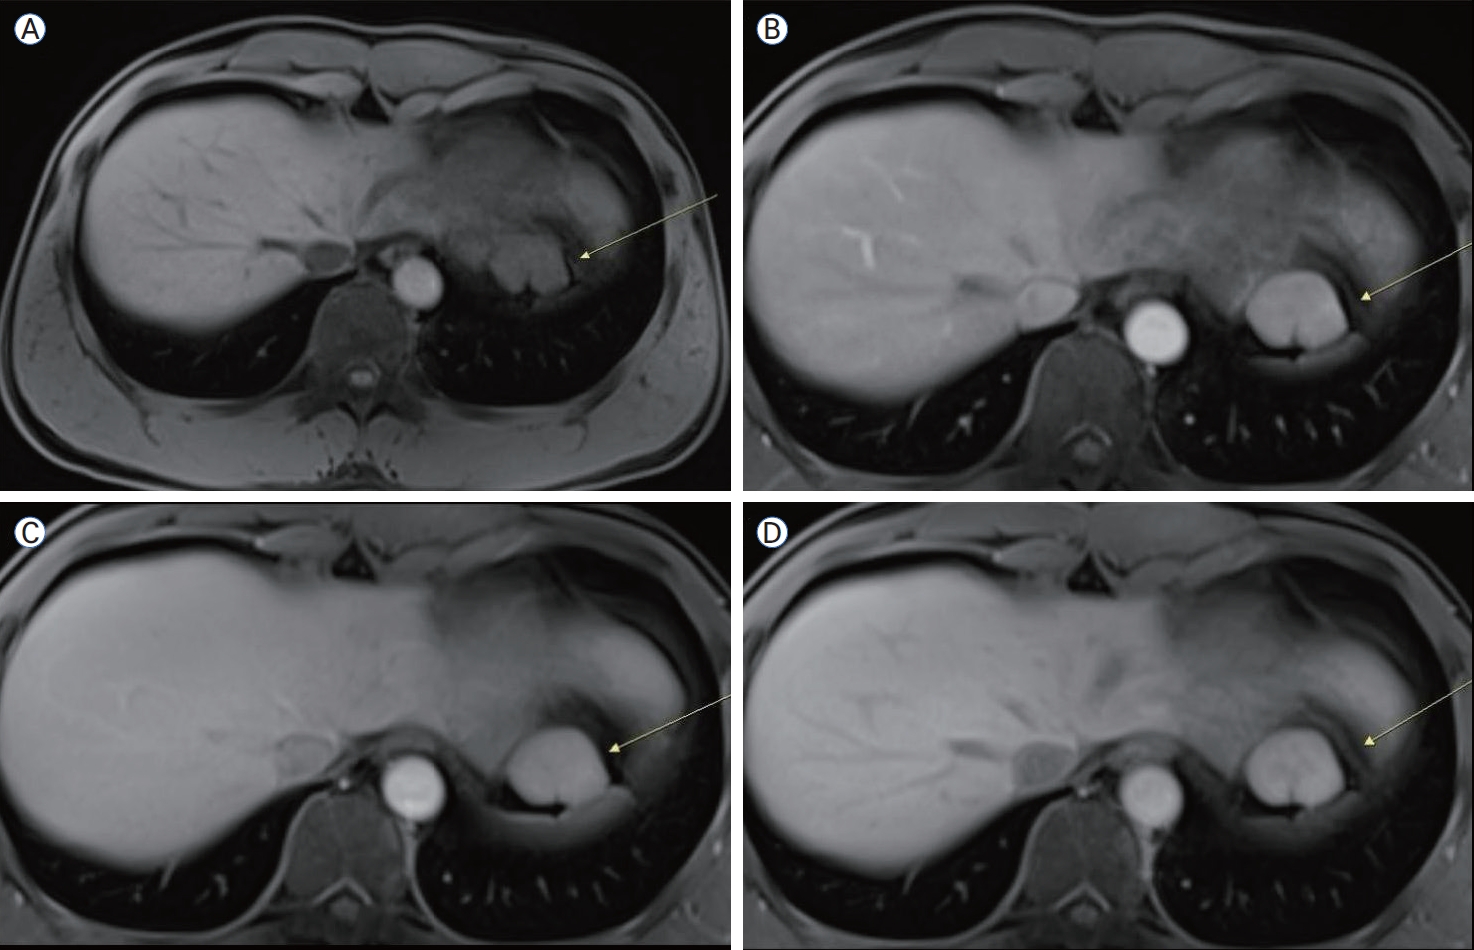

간 자기공명영상(magnetic resonance imaging, MRI)을 시행한 결과 병변은 arterial phase에서 조영증강되고 delayed phase에서 중심성 반흔을 시사하는 저신호 영역이 관찰되었는데, 이는 FNH의 전형적인 영상 소견과 일치하였다. 이러한 소견은 병변의 간 유래 가능성을 강력히 시사하였다(Fig. 4).

Figure 4.

Liver MRI findings. Pre-contrast T1 image showing low-signal (A), arterial (B), venous (C), and delayed-phase (D) images demonstrating progressive enhancement and a central scar (yellow arrows). MRI, magnetic resonance imaging.